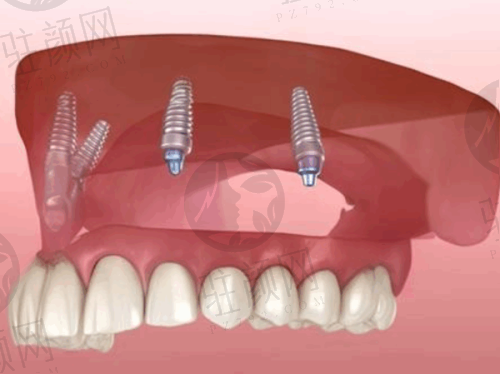

数字化种植牙技术是拜博口腔在引入数字化种植牙技术基础上,考究东方人的口腔特性,以数字化为主导,在计算机上重建患者口腔三维立体模型,凭借由3D打印技术制作的种植导板对手术全程把控。其优势显著,大大降低了手术的时间,手术中不切开,创口小,无需缝合降低痛苦 ,减少了术后肿胀和不适疼痛感,能实现对缺牙的修复。该技术采用的种植体包括瑞典诺贝尔种植系统、瑞士瑞典ITI种植系统、德国费亚丹种植系统、韩国登腾种植系统、德国ICX种植系统。

实例一:李先生,50岁,因牙齿缺失多年影响咀嚼和美观,来到深圳泰康拜博口腔门诊部(华强北店)。院长李满园为其进行了详细的检查和评估后,决定采用数字化种植牙技术进行全口种植。手术过程顺利,创口小,李先生术后修复快,疼痛感较轻。经过一段时间的修复,李先生重新拥有了健康的牙齿,咀嚼功能得到了极大改善,面容也更加饱满,他对治疗成效非常满意。